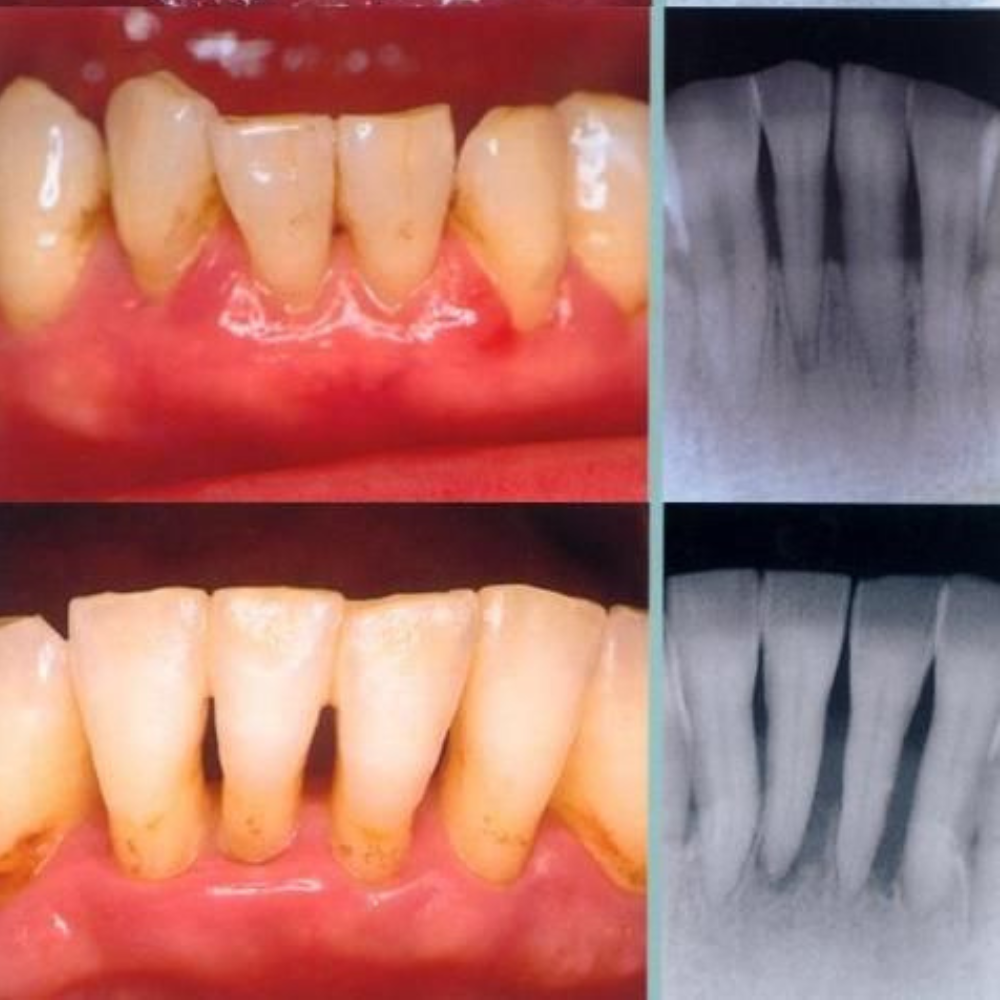

- Gingivitis: inflamación y sangrado de encías (etapa inicial y reversible)

- Periodontitis: infección más avanzada que afecta el hueso y puede provocar movilidad dental (irreversible)

- Diagnóstico (sondaje, radiografías)